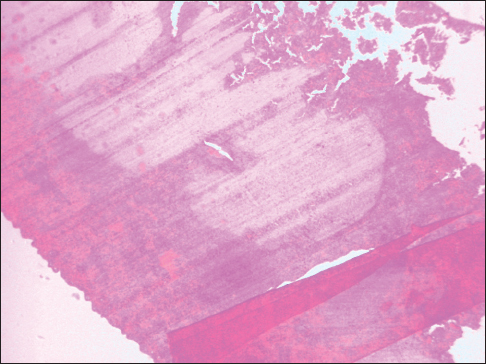

Figure 5: Knife lines and fold artifact in a section of the spleen, ×40